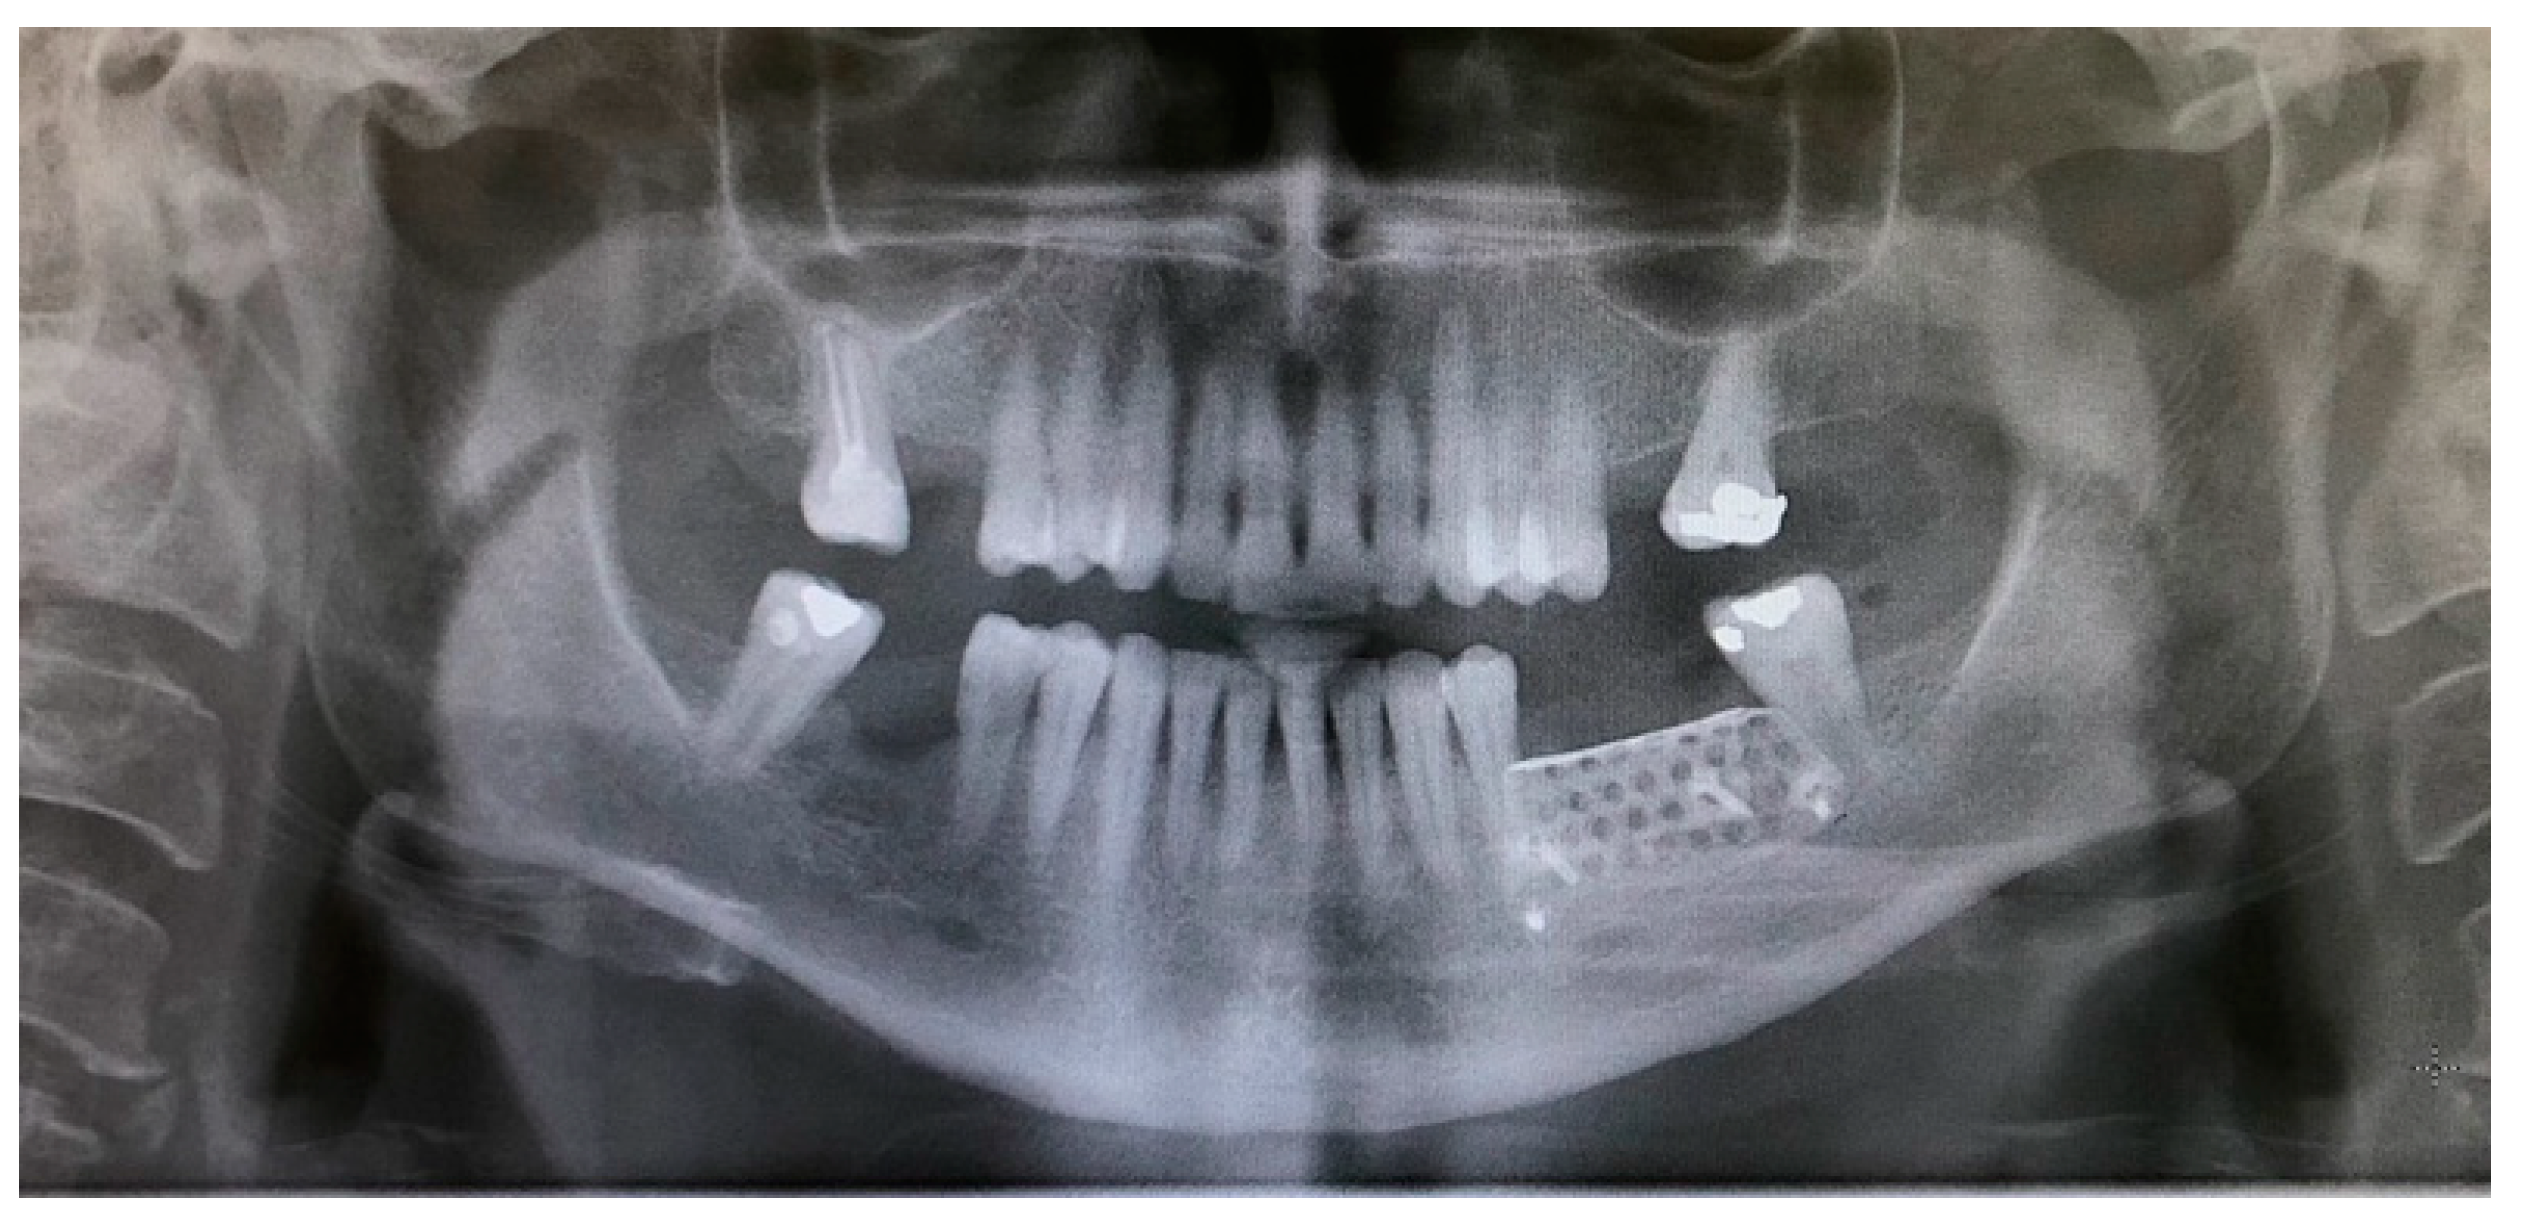

- The sutures were removed on day 21. A panoramic radiograph was taken after surgery. (Figure 8). Periodic controls were scheduled; every week during the first 2 months, every two weeks in the third and fourth months, and once a month up to 6 months.

- On the day of surgery, the titanium mesh and the microscrews were removed (Figure 9). When the mesh was removed, a soft consistency was observed in the most coronally newly formed bone and it was decided to postpone the placement of the implants and allow it to ossify for another month and a half. A panoramic radiograph was taken after surgery (Figure 10).